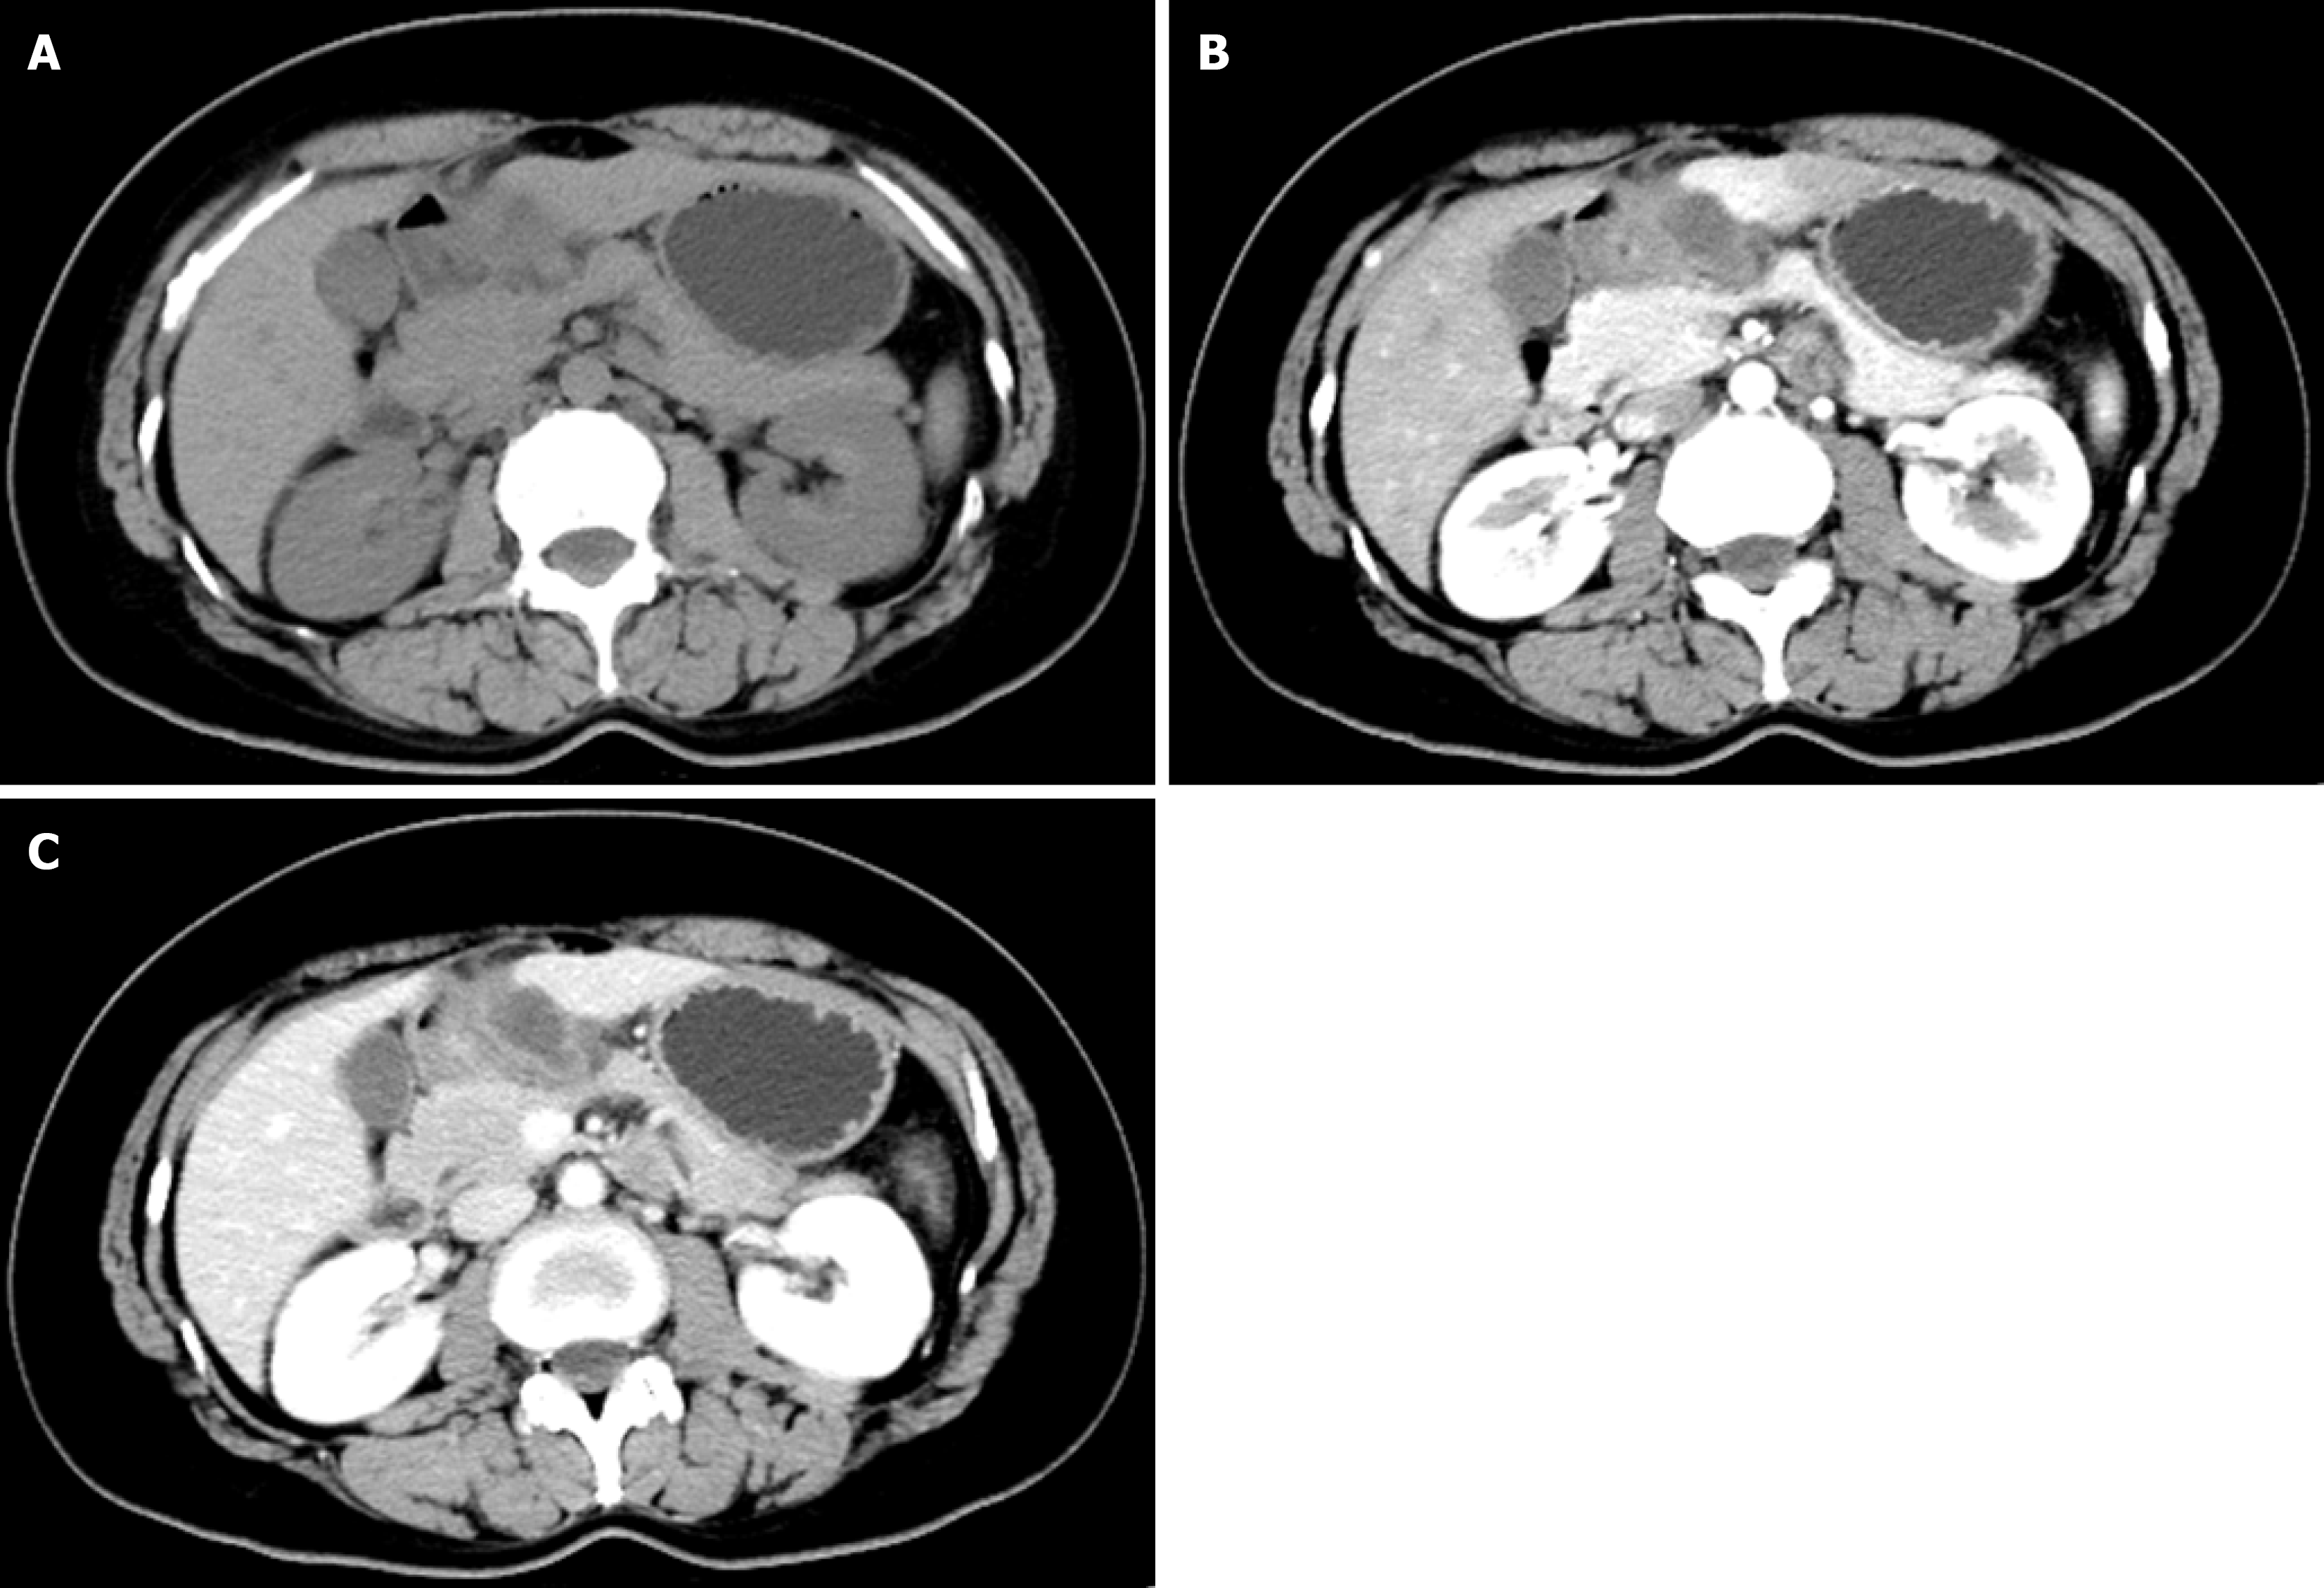

Contrast-enhanced abdominal CT demonstrated irregular thickening of the gastric antral wall with heterogeneous enhancement. A cystic lesion (3.4 cm × 2.2 cm) was found adjacent to the lesser curvature of the gastric antrum, exhibiting thick-walled morphology, blurred margins, and mild enhancement post-contrast (Figure 1). Two omental nodules near the inferior liver margin and enlarged lymph nodes in the hepatogastric ligament and mesentery were observed. MRI revealed an abnormal signal lesion (2.8 cm × 1.5 cm) lateral to the lesser curvature of the gastric antrum, showing hyperintensity on T1 weighted imaging (T1WI) (Figure 2), hypointensity on T2 weighted imaging (T2WI) (Figure 2), and no enhancement post-contrast (Figure 2). The vertical-axis ultrasound gastroscopy scan shows a uniform echo in the gastric body. A low-echo mass-like change approximately 3.0 cm × 2.2 cm in size is observed on the outer wall of the gastric antrum (Figure 3), with uneven internal echoes and visible high-echo structures (Figure 3). Based on the imaging findings, a hematoma or inflammatory lesion was suspected, with malignancy not excluded.

AA may be identified on enhanced CT or MRI due to the characteristic internal structural features on contrast-enhanced CT or T1-weighted MRI, namely “swirling”, and the low-signal band structure of fibrovascular tissue can also be shown on T2WI. However, compared with CT, MRI can show the margins of the tumor relative to the surrounding structures, especially the dynamic contrast-enhanced sequence, so it is more helpful for preoperative assessment of the scope of surgery[21].

In this case, AA grew outside the gastric wall, and no characteristic “whirlpool” pattern was seen on CT and MRI. In addition, AA showed cystic lesions on CT, without the characteristic whirlpool sign of AA in the perineum. Therefore, we speculate that the previous typical AA imaging findings cannot be used for AA in rare sites such as the gastric wall.